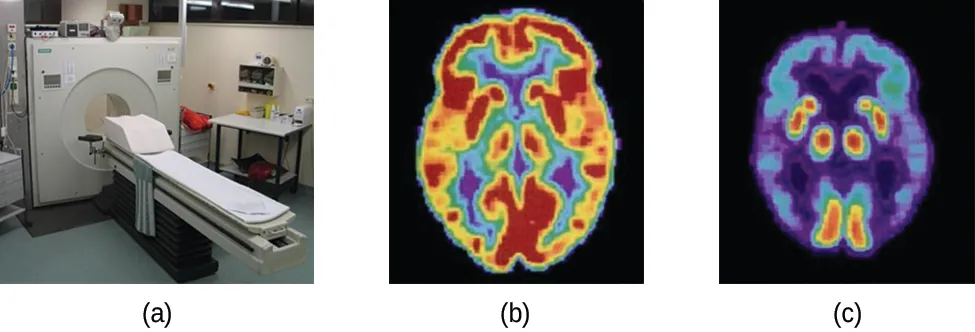

Positron emission tomography (PET) scans use radiation to diagnose and track health conditions and monitor medical treatments by revealing how parts of a patient’s body function (Figure 21.8). To perform a PET scan, a positron-emitting radioisotope is produced in a cyclotron and then attached to a substance that is used by the part of the body being investigated. This “tagged” compound, or radiotracer, is then put into the patient (injected via IV or breathed in as a gas), and how it is used by the tissue reveals how that organ or other area of the body functions.

Three pictures are shown and labeled “a,” “b” and “c.” Picture a shows a machine with a round opening connected to an examination table. Picture b is a medical scan of the top of a person’s head and shows large patches of yellow and red and smaller patches of blue, green and purple highlighting. Picture c also shows a medical scan of the top of a person’s head, but this image is mostly colored in blue and purple with very small patches of red and yellow.

Figure 21.8 A PET scanner (a) uses radiation to provide an image of how part of a patient’s body functions. The scans it produces can be used to image a healthy brain (b) or can be used for diagnosing medical conditions such as Alzheimer’s disease (c). (credit a: modification of work by Jens Maus)

For example, F-18 is produced by proton bombardment of 18O ( 818O + 11p 918F + 01n )( 818O + 11p 918F + 01n ) and incorporated into a glucose analog called fludeoxyglucose (FDG). How FDG is used by the body provides critical diagnostic information; for example, since cancers use glucose differently than normal tissues, FDG can reveal cancers. The 18F emits positrons that interact with nearby electrons, producing a burst of gamma radiation. This energy is detected by the scanner and converted into a detailed, three-dimensional, color image that shows how that part of the patient’s body functions. Different levels of gamma radiation produce different amounts of brightness and colors in the image, which can then be interpreted by a radiologist to reveal what is going on. PET scans can detect heart damage and heart disease, help diagnose Alzheimer’s disease, indicate the part of a brain that is affected by epilepsy, reveal cancer, show what stage it is, and how much it has spread, and whether treatments are effective. Unlike magnetic resonance imaging and X-rays, which only show how something looks, the big advantage of PET scans is that they show how something functions. PET scans are now usually performed in conjunction with a computed tomography scan.